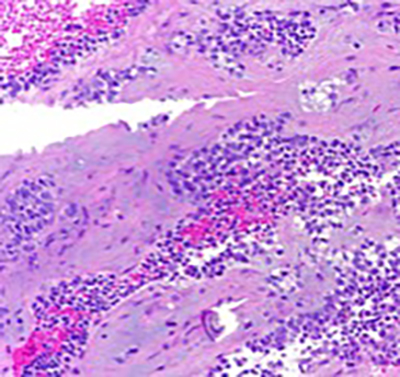

The aspirate was hypercellular and composed of small round cells, distributed in clusters of loosely cohesive clusters and as isolated cells. Moderate pleomorphism, hyperchromasia and variably prominent nucleoli were noted. On cell block preparation, the cytoplasm of these cells had a cleared appearance. Geographic necrosis was noted, with viable cells present in perivascular areas. Focally, there was an extracellular myxoid matrix.

Cell block preparation (200X)

The differential diagnosis is vast and includes many tumors that can present as small round cells, including conventional Ewing sarcoma. Recent studies have shown that CIC-DUX4 fusion sarcomas are clinically and morphologically different from Ewing sarcoma. CIC-DUX4 fusion sarcoma tends to arise deep in the soft tissue and in older patients (median: 40 years old), whereas Ewing sarcoma (median: 15 years old) arises in the bone in younger patients. Morphologically, the tumor cells exhibit mild pleomorphism, vesicular chromatin with variably prominent nucleoli, moderate amount of light eosinophilic cytoplasm and stroma with myxoid change. This is in contrast to Ewing sarcoma, which is usually monotonous with inconspicuous nucleoli. The immunohistochemical profile is also different. CD99 shows strong membranous staining in Ewing sarcoma, but is weak and variable in CIC-DUX4 fusion sarcoma. WT1 is usually negative in Ewing but is positive in most cases of CIC-DUX4 sarcoma. Recently, DUX4 immunohistochemistry has been shown to be positive, reflecting the fusion driving tumorigenesis. Molecular testing is ultimately required to identify one of the diagnostic translocations.